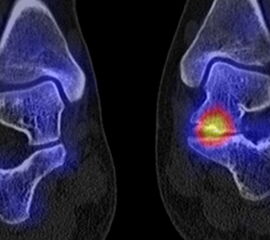

Die Abbildungen 4.2.a bis d zeigen den typischen Aspekt einer talacalcanearen Coalitio. Es besteht nur eine linksseitige, symptomatische Coalitio talocalcaneare (4.2.a und c); das 35 Tage zuvor angefertigte MRT zeigt keine auffälligen Signalveränderungen (4.2.b und d).

Abbildung 4.3. zeigt die Ursache für rechtsseitige Sprunggelenksbeschwerden bei einem Patienten mit talocalcanearen Coalitionen: nur die osteochondrale Läsion an der distalen rechten Tibia ist die Ursache des Schmerzes. Die bilateralen talocalcanearen Coalitionen sind asymptomatisch.